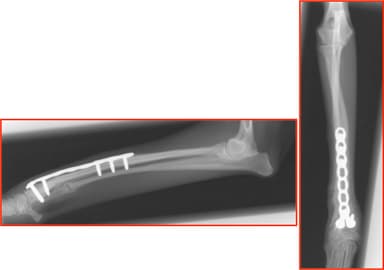

・前足は、横方向に36.8°外側へ向き(外反変形)、前後方向に10.2°手前に曲がっていた(前屈変形)。

術前X線画像1

http://www.atpress.ne.jp/releases/54567/img_54567_2.jpg

術前X線画像2

http://www.atpress.ne.jp/releases/54567/img_54567_3.jpg